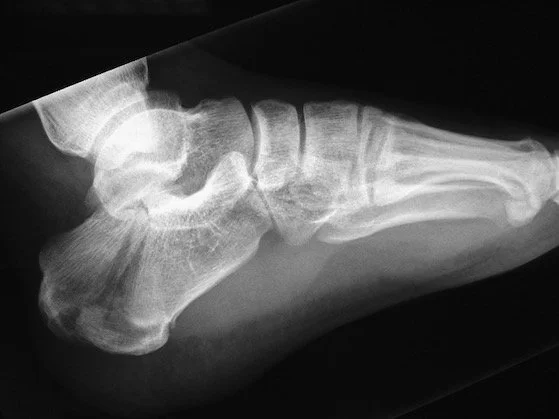

Hindfoot Fractures

• Calcaneal (Heel) Fractures: Often caused by falls from height.

• Talar Fractures: Serious injuries affecting the "plug" of the ankle joint.